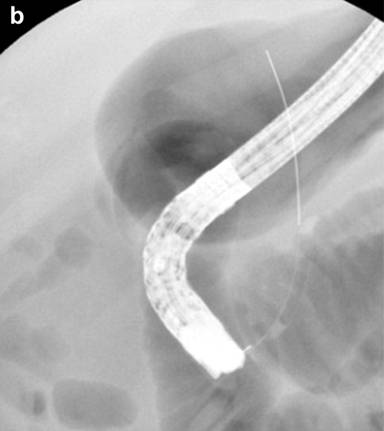

Prophylactic stenting of the pancreatic duct (Figure 2a) has been shown to decrease the risk of PEP in several situations, including SOD, precut sphincterotomy, balloon dilation of the biliary sphincter, ampullectomy, and pancreatic guidewire assisted cannulation of the bile duct [30, 35, 36]. Prophylactic stenting should be considered in all patients prior to performing precut sphincterotomy. This is supported by data showing that the rate of PEP is only 4.3% when precut sphincterotomy for biliary access is performed over a pancreatic stent [37]. It is also thought that the stent may help delineate the ductal anatomy and assist in selective cannulation of the biliary orifice after precut sphincterotomy. There is also data to suggest that pancreatic duct stenting may be protective in all patients undergoing ERCP [38]. However, the standard of care for prophylactic stenting remains in patients at high risk of PEP. This is also corroborated by a cost-effectiveness analysis, which demonstrates the superiority of prophylactic stenting in patients at high risk of PEP compared to stenting all patients or no patients undergoing ERCP [39].

Figure 2. Pancreas stenting (a.) in high risk cases and wire guided approaches (b.) are technical manoeuvres which minimize the risk of PEP. |

Cannulation Techniques

Cannulation using a guidewire (Figure 2b) rather than contrast-directed cannulation is considered a valuable technique in preventing PEP. This enables access to the desired duct using a soft-tipped guidewire, while avoiding contrast injection into the pancreatic duct. It is also thought that inadvertent advancement of a guidewire into the pancreatic duct may be less traumatic to the pancreas than contrast opacification. Wire-guided cannulation first received considerable attention when a prospective study randomized 400 patients to wire-guided cannulation versus conventional contrast directed cannulation. Cannulation success rates were similar, but no PEP developed in the guidewire group, whereas PEP occurred in 4% in the contrast group (P<0.01) [44]. Since then, several studies have indicated that wire-guided cannulation reduces the risk of PEP. Subsequent large randomized trials have consistently demonstrated PEP rates of 2-9% in wire-guided versus 10-17% in contrast guided ERCP [44-46], which has also been supported by several meta-analyses [47-50]. However, there is some heterogeneity in the data [47] and the wire-guided technique has come under scrutiny as two recent prospective studies have not shown a reduction in rates of PEP [51, 52]. There may be several reasons for the mixed data on wire-guided cannulation. First, the endoscopists performing the procedures in these studies may have variable experience with one particular technique, which can potentially bias the data. The second reason is that “wire-guided cannulation” is not a single technique, but rather a method of cannulation that can be performed in many different ways. Pure wire-guided cannulation involves introducing the wire into the biliary orifice, while keeping the tip of the sphincterotome in the duodenal lumen. Another variation of wire guided-cannulation is when the tip of the cannula is inserted into the common channel and the wire is gently probed back and forth at varying angles until the biliary orifice is entered. The wire can be controlled by the assistant or by the physician. A hybrid method also exists, where the desired duct is first opacified with contrast, then the guidewire is used to access the duct [30]. Most advanced endoscopists use a combination of these methods, making generalization of studies on wire-guided cannulation problematic. However, based on the abundance of favorable data, it is reasonable to conclude that the wire-guided technique should be considered a first-line modality for cannulation.